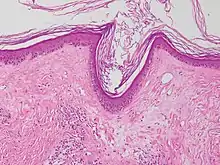

| Micrograph of lichen sclerosus showing the characteristic subepithelial sclerosus (right/bottom of image). H&E stain. | |

A biopsy of the affected skin can be done to confirm diagnosis. When a biopsy is done, hyperkeratosis, atrophic epidermis, sclerosis of dermis and lymphocyte activity in dermis are histological findings associated with LS.[22] The biopsies are also checked for signs of dysplasia.[23]